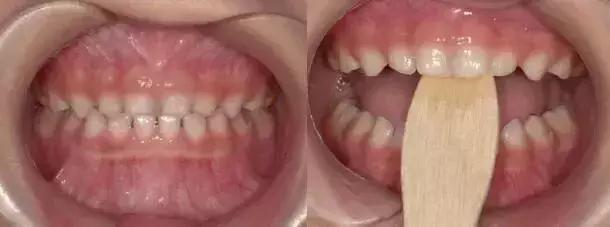

咬撬法

没得错,就是喊你咬棍棍儿!选择压舌板或牙刷柄,每天咬撬木板三次,每次大约2分钟(约20下),每两周复诊,1-3个月就阔以有效纠正“地包天”。